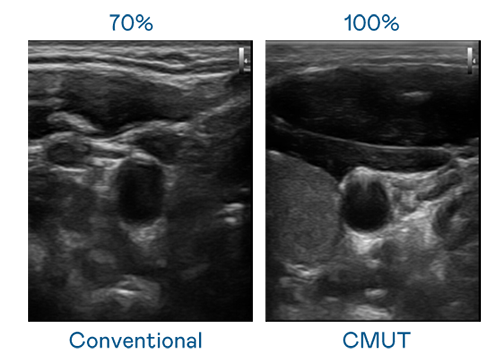

CMUT 技术是一种用电容式微机电元件来产生超音波讯号的技术。与传统 PZT 压电式技术相比,CMUT 频宽增加 30%,更宽频的超音波讯号让影像解析度大幅提升,是实现高影像品质医疗超音波扫描、促进精准医疗发展的关键技术。

大频宽带来超清晰影像

超音波影像的解析度高低,首先取决于探头能发出的讯号频宽。麻花豆电影高清 CMUT 可提供高清晰的超音波讯号,提供高频宽、高灵敏度、影像纹理细节更高的超音波影像,协助医护人员缩短影像判读时间及利用精准的医疗影像进行诊断。